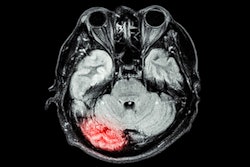

Hyperfine has begun the commercial launch of its latest Optive AI software used on its Swoop portable MRI system for brain imaging.

Optive AI improves each stage of the imaging process, from noise cancellation and image acquisition to reconstruction and postprocessing, the company said. Hyperfine has begun rolling out the new software to hospitals and outpatient neurology offices in the U.S., with plans to bring it to all current customers in the coming weeks.